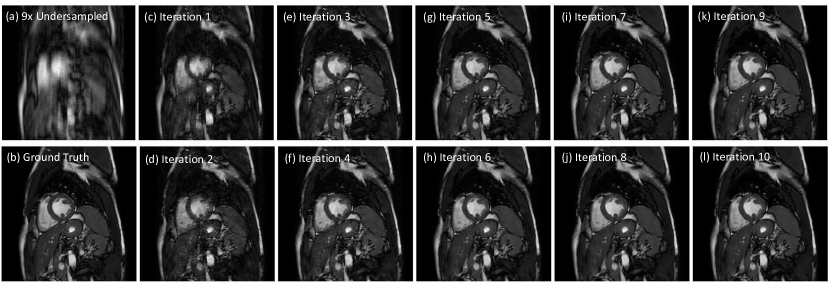

The comparison results of all methods are reported in Table I, where we evaluated the quantitative metrics, network capacity and reconstruction time. Numbers shown in Table I are mean values of corresponding metrics with standard deviation of different subjects in parenthesis. Bold numbers in Table I indicate the better performance of the proposed methods than the competing ones. Compared with the baseline method (k-t FOCUSS and k-t SLR), the proposed methods outperform them by a considerable margin at different acceleration rates. When compared with deep learning methods, note that the network capacity of Proposed-A is comparable with that of 3D CNN-S and the capacity of Propose-B is around one third of that of 3D CNN. Though their capacities are much smaller, both Proposed-A and Proposed-B outperform 3D CNN-S and 3D CNN for all acceleration rates by a large margin, which shows the competitiveness and effectiveness of our method. In addition, we can see a substantial improvement of the reconstruction results on all acceleration rates and in all metrics when the number of network parameters is increased for the proposed method (Proposed-B), and therefore we will only show the results from Proposed-B in the following. The number of iterations used by the network at test time is set to be the same as the training stage, which is N=10𝑁10N=10, however, if the iteration number is increased up to N=17𝑁17N=17, it shows an improvement of 0.324dB on average. Fig. 3 shows the model’s performance varying with the number of iterations at test time. Similarly, visualization results of intermediate steps during the iterations of a reconstruction from 9×\times undersampling data are shown in Fig. 4, where we can observe the gradual improvement of the reconstruction quality from iteration step 1 to 10, which is consistent with the quantitative results as in Fig. 3.

Figure 4: Visualization results of intermediate steps during the iterations of a reconstruction. (a) Undersampled image by acceleration factor 9 (b) Ground Truth (c-l) Results from intermediate steps 1 to 10 in a reconstruction process.